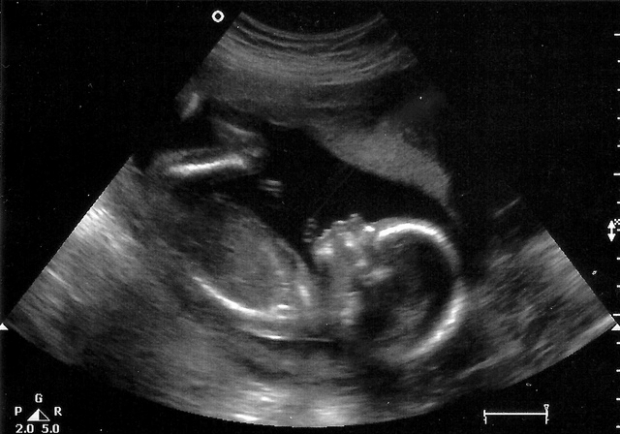

Начался третий и заключительный триместр беременности. Вес плода уже превышает один килограмм. На ультразвуковом исследовании специалисты оценивают его размеры и положение в матке. С этой недели малыш начинает занимать ту позицию, из которой, скорее всего, будет рожден. Тем не менее, если на УЗИ врач сообщил, что ребенок находится в неправильном положении, не стоит паниковать — в матке все еще достаточно пространства, чтобы он мог изменить свою ориентацию.